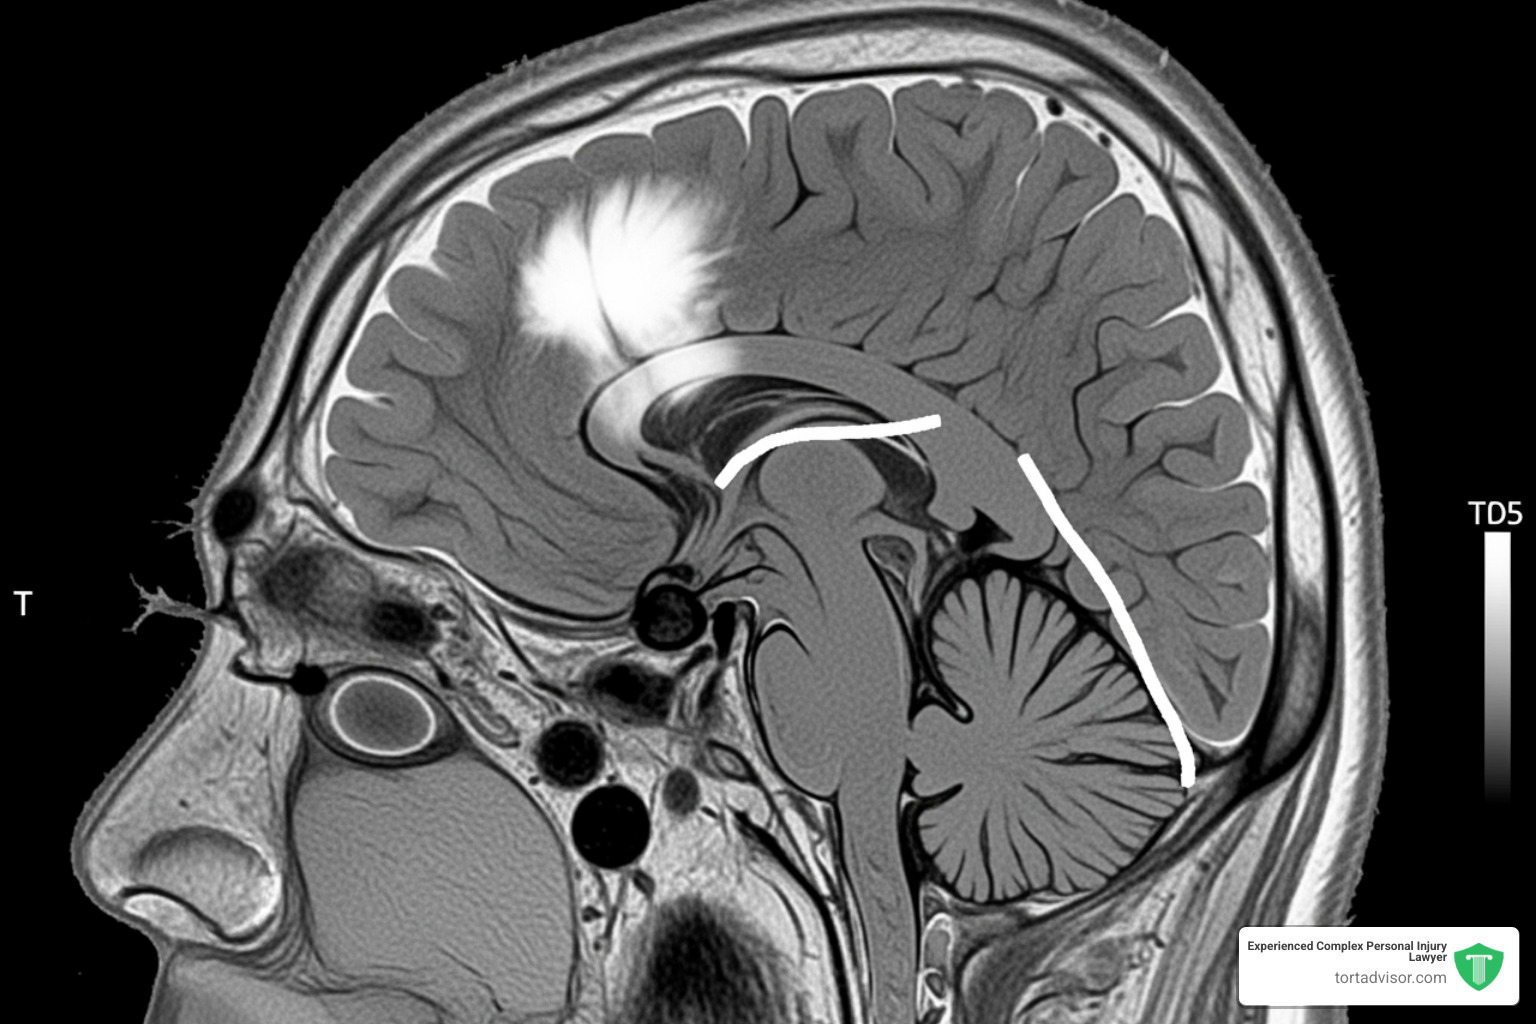

The most serious claim involves meningiomas, tumors that grow in the protective tissues surrounding the brain and spinal cord. These are the most common type of primary brain tumor and occur more often in women, suggesting a hormonal link.

While most meningiomas are non-cancerous, their growth inside the skull can cause severe problems by pressing on the brain. Symptoms can be life-altering and include:

Treatment often involves a craniotomy, a major brain surgery to remove the tumor. Some patients, like Robin Phillip, have required multiple surgeries and been left with permanent disabilities like vision loss. These are not minor side effects; they are devastating injuries. The link between Depo-Provera and these tumors is the central issue driving the litigation. Our Depo Shot Brain Tumor page explores this connection further.

The depo-provera lawsuit litigation is supported by compelling scientific evidence. The biological mechanism is plausible: meningioma tumors often have progesterone receptors on their surface. The synthetic hormone in Depo-Provera, medroxyprogesterone acetate (MPA), may bind to these receptors and stimulate tumor growth.

- Proof of Injury: All medical records related to your meningioma diagnosis and treatment, including MRIs, CT scans, pathology reports, and surgical notes.